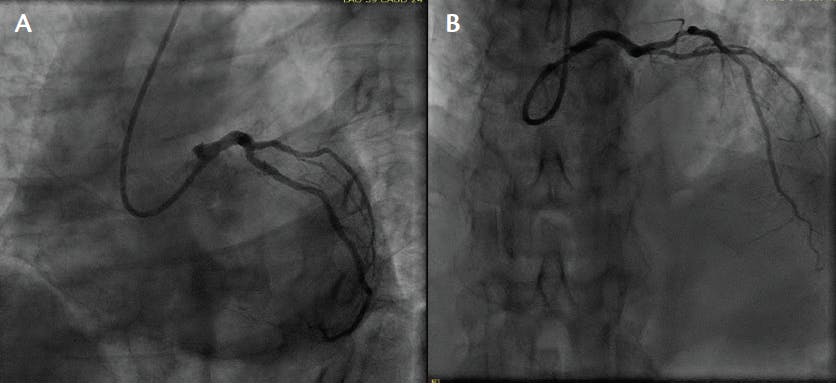

A man in his late 40s with a history of daily cigarette smoking presented to the ED with retrosternal chest pain. ECG was performed and showed evolving anterior ST-segment changes and high-sensitivity troponin at 1300 ng/L, and a bedside echocardiogram showed an LVEF of 30% with anteroseptal wall motion abnormalities. A coronary angiogram showed a 100% proximal LAD occlusion (Figure 1) and primary PCI with a 40- X 28-mm drug-eluting stent achieving good angiographic results (Figure 2). SSO2 protocol was implemented immediately after PCI.

Figure 1. LAO caudal (A) and RAO (B) cranial views before PCI.